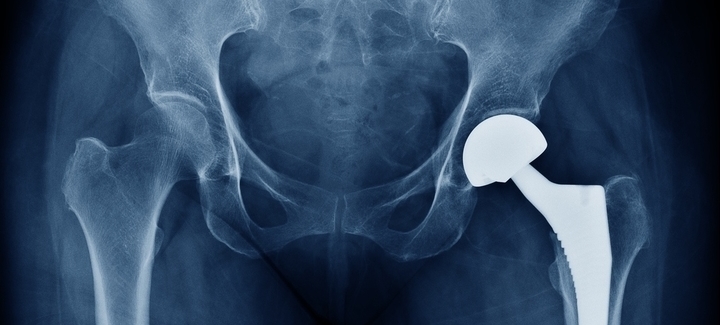

Scientists have discovered how the materials used in medical implants like artificial joints can be adapted to control the immune response to them and reduce the risk of rejection.

The team from the University of Nottingham’s Schools of Pharmacy and Life Sciences have found that the surface shape (topography) and chemical composition of polymer materials can be changed to create materials that control the body’s immune response. This could have future applications in the fight against rejection of medical devices including artificial joints, dental implants and vascular implants. The results from two recent studies have been published in Advanced Science and Matter.